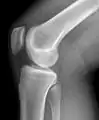

Рентгенологическое исследование коленных суставов

Самым доступным, одним из информативных и распространённых исследований является рентгенологическое исследование.

Стандартные проекции, применяемые при рентгенографии коленного сустава — прямая (передне-задняя) и боковая. По мере необходимости их дополняют правой или левой косой, а также аксиальной проекциями. Основным правилом при рентгенологическом исследовании коленного сустава является полипозиционность[2][3].

На рентгенограммах между суставными поверхностями костей видна так называемая рентгеновская суставная щель. Рентгеновской она называется потому, что, будучи заполненной хрящом и прослойкой синовиальной жидкости, которые не дают изображения на рентгенограммах, она имеет вид более прозрачной полосы между суставными поверхностями.

Рентгенограмма коленного сустава в боковой проекции.